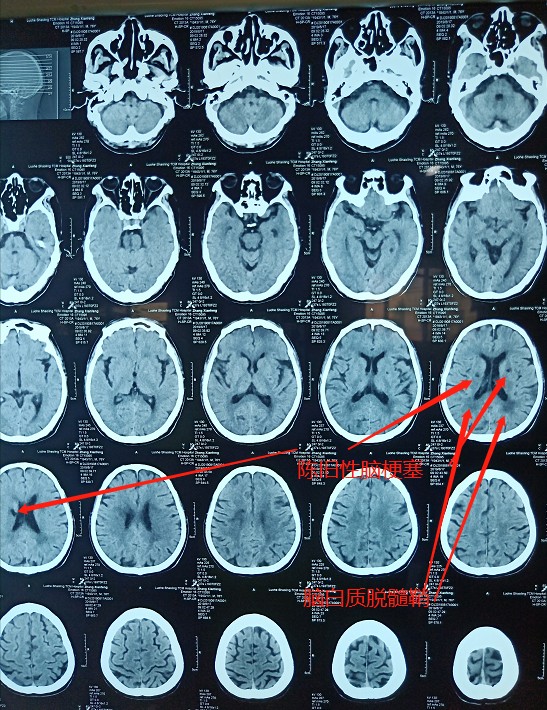

颅脑CT显示:陈旧性脑梗死。